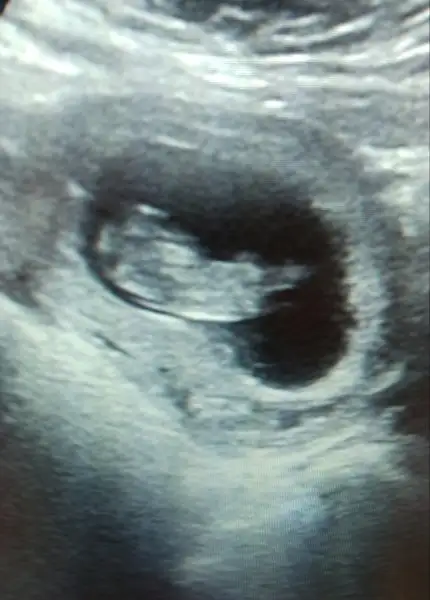

Ne güzel.ben doktora gittim alttan baktı gene biraz bastirdi göremeyince minik çok küçük bi yuvarlak gördüğünü söyledi ben göremedim gösterti ama anlamadim bebek kese olusturmamis dedi hcg istedi orda belli olur dedi bide gebelikde yapılan testleri istedi onlar ayın altısında çıkacakmış hcg birde alcam sonucu inş yükselmiştir yaEvet canim 11 haftalik :) evet genç olmak istemiştim hep

Hcg hemen cikar yükselir. Merak etmeNe güzel.ben doktora gittim alttan baktı gene biraz bastirdi göremeyince minik çok küçük bi yuvarlak gördüğünü söyledi ben göremedim gösterti ama anlamadim bebek kese olusturmamis dedi hcg istedi orda belli olur dedi bide gebelikde yapılan testleri istedi onlar ayın altısında çıkacakmış hcg birde alcam sonucu inş yükselmiştir ya

Yok demekki ufacik bisi gördü o da kanamam geliyordu aslında düşük ilacı içince kanama engellendi orda kan birikti herhalde yada bebek yerini yapamadı hcg düştü o yuzden inşallah kanamam söker de operasyona gerek kalmazNasil yani bebek yokmu bos gebelikmi